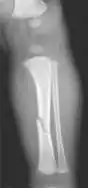

The material factual allegations of the amended complaint are as follows. Plaintiff was born on May 14, 1970. On repeated occasions during the first year of her life she was severely beaten by her mother and the latter's common law husband, one Reyes. On April 26, 1971, when the plaintiff was eleven months old, her mother took her to the San Jose Hospital for examination, diagnosis, and treatment. The attending physician was defendant Dr. Flood, acting on his own behalf and as agent of the defendant San Jose Hospital. At the time, the plaintiff was suffering from a comminuted spiral fracture of the right tibia and fibula, which gave the appearance of having been caused by a twisting force. Plaintiff's mother had no explanation for this injury. Plaintiff had bruises over her entire body. In addition, she had a non-depressed linear skull fracture which was then in the process of healing. Plaintiff demonstrated fear and apprehension when approached. Inasmuch as all plaintiff's injuries gave the appearance of having been intentionally inflicted by other persons, she exhibited the medical condition known as the battered child syndrome.